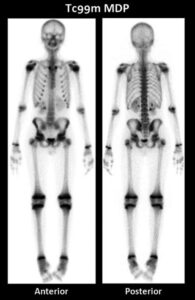

Mentre spesso viene associata all’oncologia, la medicina nucleare riveste un ruolo altrettanto cruciale e dinamico nella diagnosi e gestione delle patologie benigne dell’apparato scheletrico. La sua forza unica risiede nella capacità di fornire una visione funzionale e metabolica dell’osso, andando ben oltre la semplice anatomia.

A differenza delle tecniche di imaging morfologico come Radiografie, TC o RM, che mostrano principalmente la struttura dell’osso, la scintigrafia ossea cattura l’attività biologica in corso.

Il radiofarmaco somministrato si fissa infatti in proporzione all’intensità del rimodellamento osseo, un processo fisiologico che viene drasticamente accelerato in risposta a un’ampia varietà di stimoli: un’infezione, una frattura, un deficit vascolare o un’infiammazione.

Questo accelerato ricambio, spesso associato a una progressiva riduzione del contenuto minerale (come nell’osteomalacia o nell’iperparatiroidismo secondario), si traduce scintigraficamente in un’assorbimento diffuso e intenso del radiofarmaco in tutto lo scheletro. Questo pattern, noto come “super scan metabolico“, è il segno distintivo di molte di queste condizioni. In un “super scan”, lo scheletro appare straordinariamente ben definito e ipercaptante, mentre l’attività renale e dei tessuti molli è marcatamente ridotta o assente, perché il tracciante viene avidamente assorbito dall’osso.